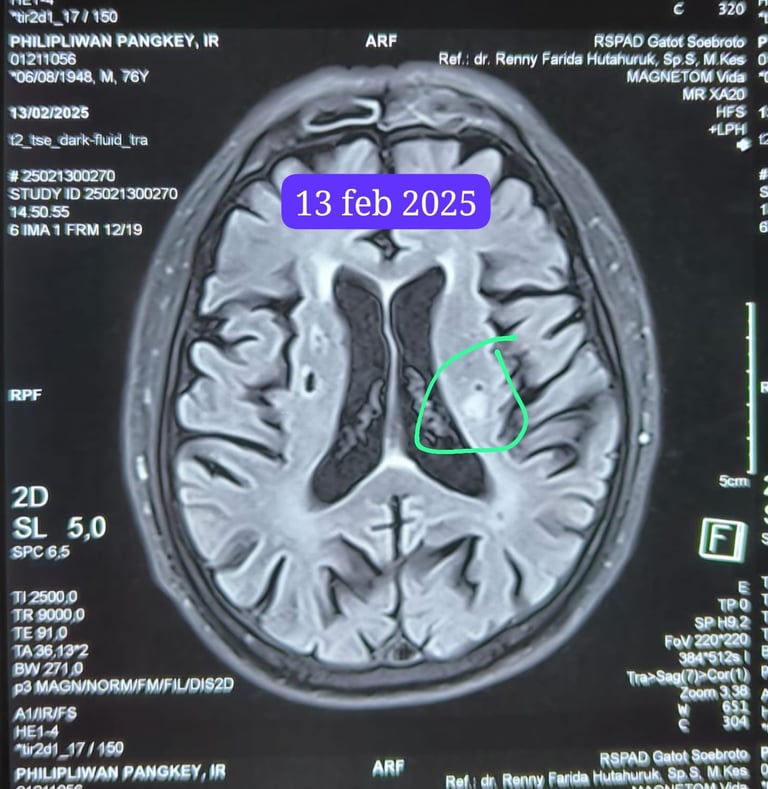

Februari 2025: Ujian Kedua

Belum sempat saya menarik napas lega, Papa terkena Stroke. Penggumpalan di otak kiri membuat tangan kanan Papa tidak bisa digerakkan, dan Papa kehilangan kemampuan untuk berjalan. Melihat sosok Ayah yang biasanya kuat dan mandiri tiba-tiba tidak berdaya adalah kesedihan yang sulit dilukiskan.